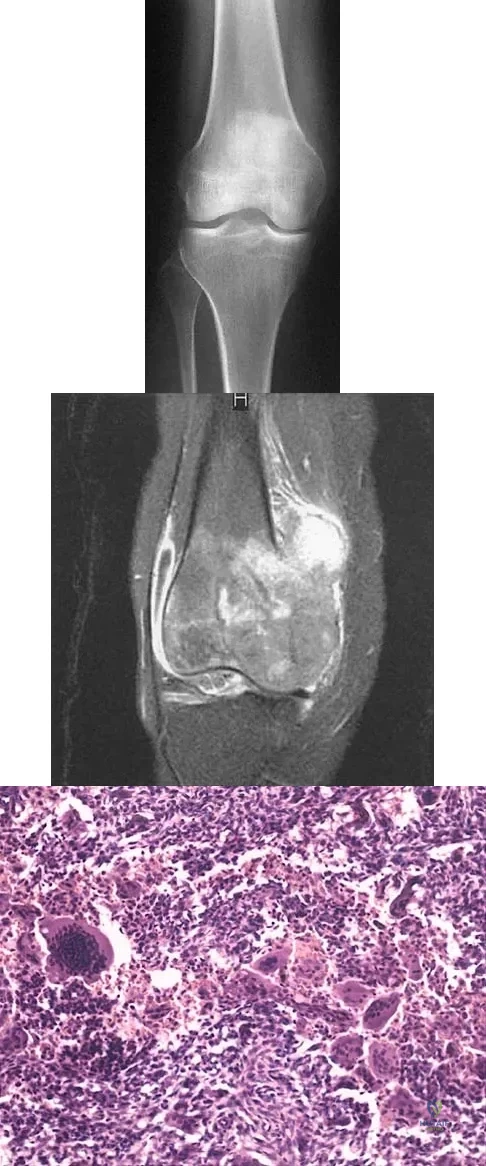

A 12-year-old girl has had progressive left knee pain for the past 4 months. She reports that the pain is unrelated to activity, and she has no history of fever or recent infections. Examination reveals full range of motion of the knee but tenderness along the medial joint line. Plain radiographs and MRI scans are shown in Figures 39a through 39d. A biopsy specimen of the lesion is shown in Figure 39e. Treatment should include